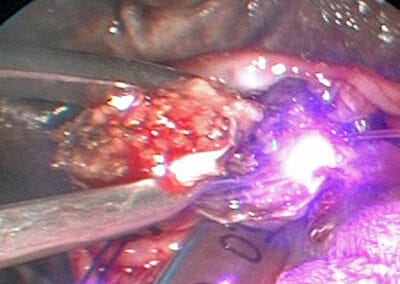

die Gaumensegelplastik mit dem Laser: das Gaumensegel chirurgisch ausgedünnt und anschließend gerafft. Eine lasergeführte Gaumensegelraffung hat den Vorteil, dass sie kaum mit Blutungen einhergeht. Die Operationszeiten verkürzt sich und die Patienten sind weniger mit Narkotika belastet.

Wir empfehlen eine Gaumensegelplastik: das Gaumensegel chirurgisch ausgedünnt und anschließend gerafft. Eine lasergeführte Gaumensegelraffung hat den Vorteil, dass sie kaum mit Blutungen einhergeht. Die Operationszeiten verkürzt sich und die Patienten sind weniger mit Narkotika belastet.